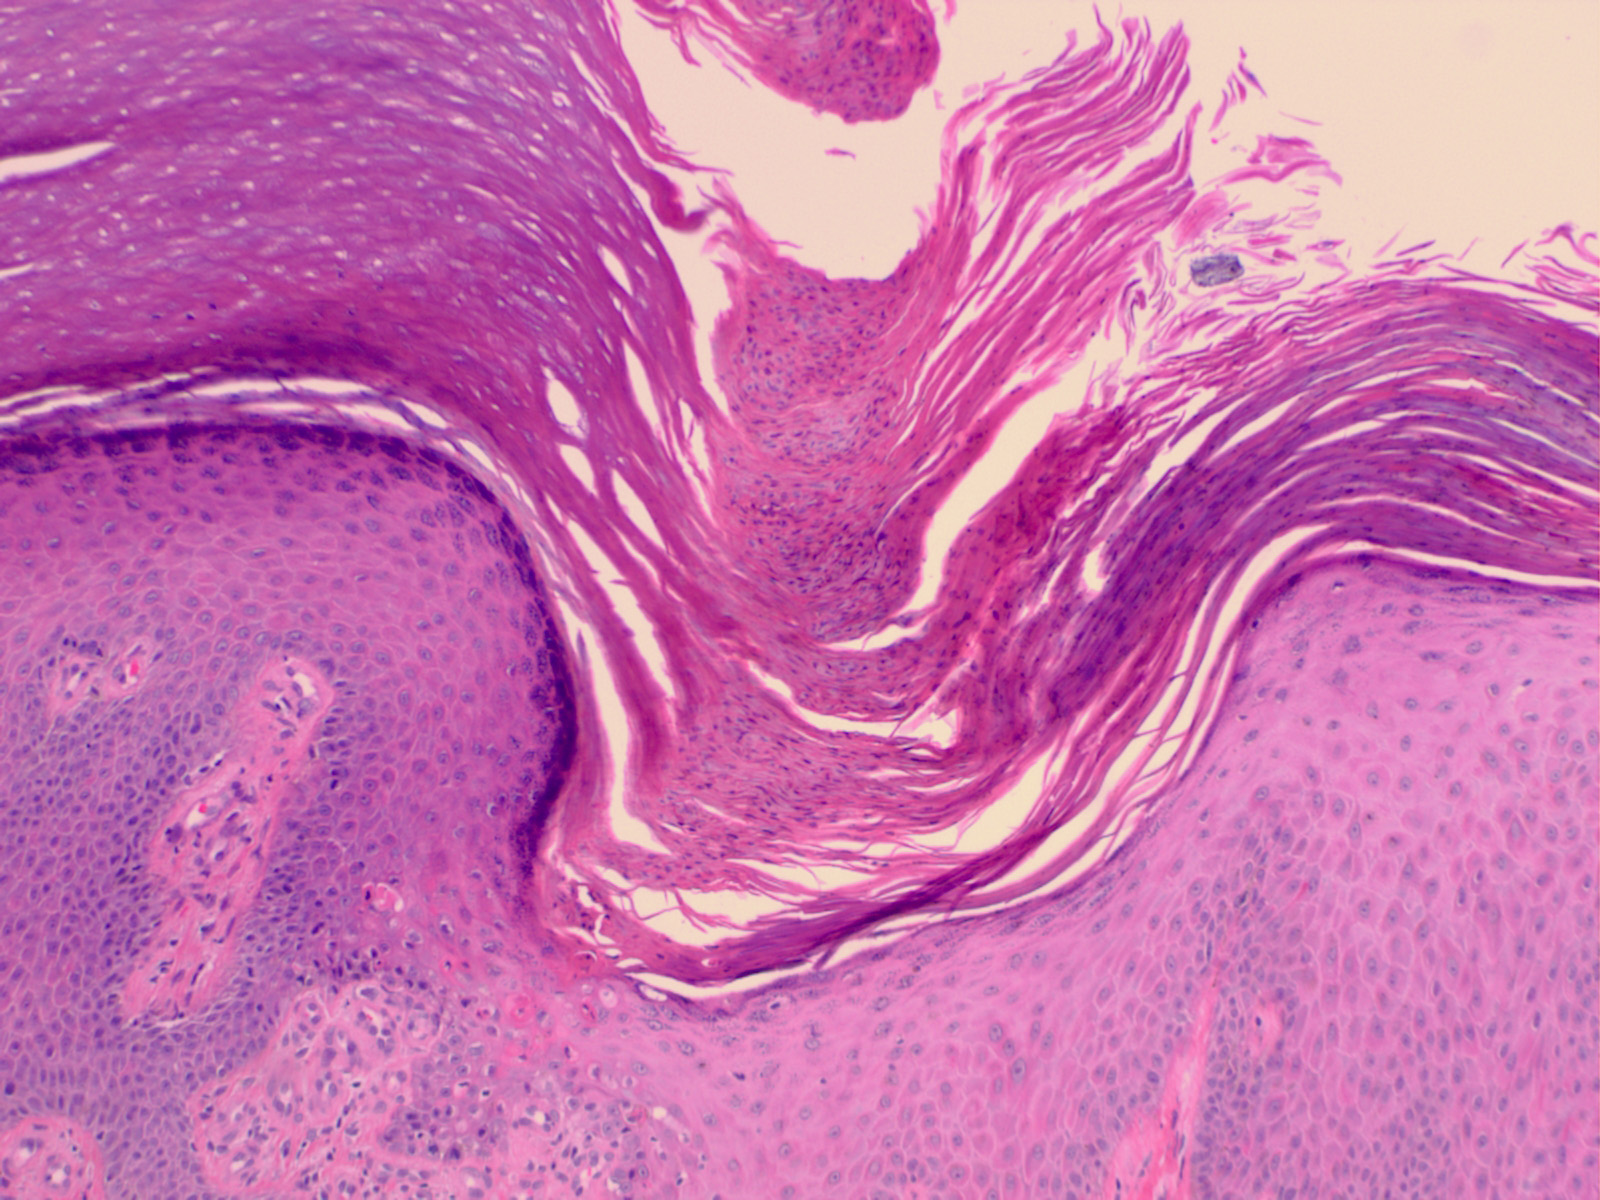

HISTOPATHOLOGY

Histopathologic patterns are similar in all forms of porokeratosis, with the characteristic changes evident at the raised and advancing edge of the lesion. The stratum corneum is hyperkeratotic, with a thin column of poorly staining parakeratotic cells, the cornoid lamella, running through the surrounding normal-staining cells . The underlying keratinocytes are edematous with spongiosis and shrunken nuclei, and a striking dermal lymphocytic pattern may be evident. Underlying the cornoid lamella, the granular layer is either absent or markedly reduced but is of normal

thickness in other areas of the lesion. The epidermis in the central portion of porokeratosis may be normal, hyperplastic, or atrophic. Although characteristic of porokeratosis, the cornoid lamella is not pathognomonic and may also be found in other conditions, such as viral warts, some ichthyoses, and nevoid hyperkeratoses.